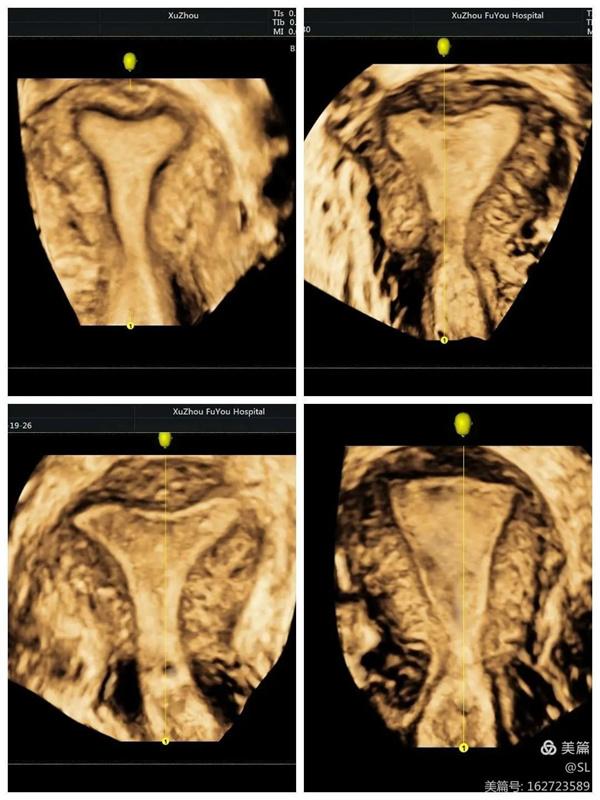

据张丽主任介绍,经阴道三维彩超是使用容积探头对宫腔内的病变及盆腔进行三维成像,可多模式重建成像,全方位、多视角完整、立体显示宫腔内部结构和空间位置关系,直观清晰的立体成像对妇科疾病的诊断更加准确,在妇科检查中得到广泛应用。

先天性子宫畸形是妇科的常见疾病,也是女性不孕不育、习惯性流产、胎儿宫内发育迟缓等疾病的主要原因之一。经阴道三维彩超在评估子宫病变等方面,提供了更丰富的影像信息。这种超声技术不仅能够更好的观察子宫外形轮廓及宫腔内膜的形态,还能清晰观察患者宫腔内的可疑部位和周围组织,帮助医生更准确的分析判断病情。

张丽主任提到,经阴道三维超声是在二维超声基础上技术升级的检查手段。二维超声是断层扫查,很难显示冠状切面,三维超声可以立体实时、从多个面来观察,提供比二维超声更丰富的信息量,因此医生根据三维彩超来诊断,结果会更加准确。